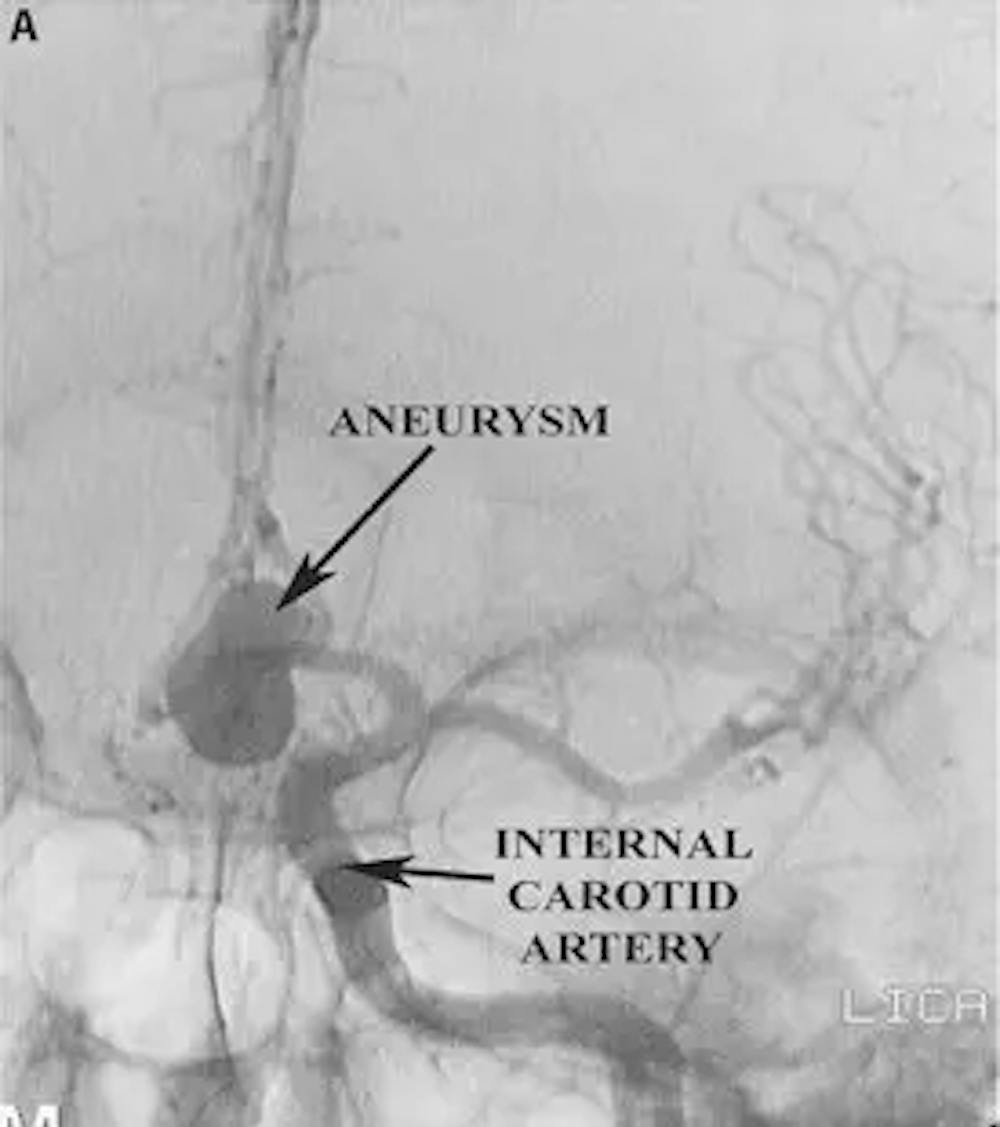

A) 수술 전 AP 혈관 조영술에서 큰 전방 소통 동맥 동맥류를 보여주는 경우